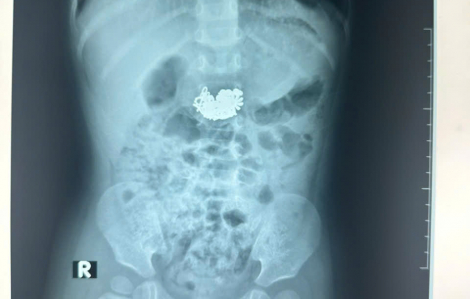

Bé trai 22 tháng tuổi khiến cả gia đình tá hỏa vì nuốt nguyên sợi dây chuyền bạc có mặt dây lớn.

Trong lúc ngậm sợi dây chuyền đang đeo trên cổ, bé trai ở Quảng Bình vô tình nuốt mặt dây chuyền là một chiếc nanh hổ dài 2cm, có bọc một lớp bạc bên ngoài vào bụng.